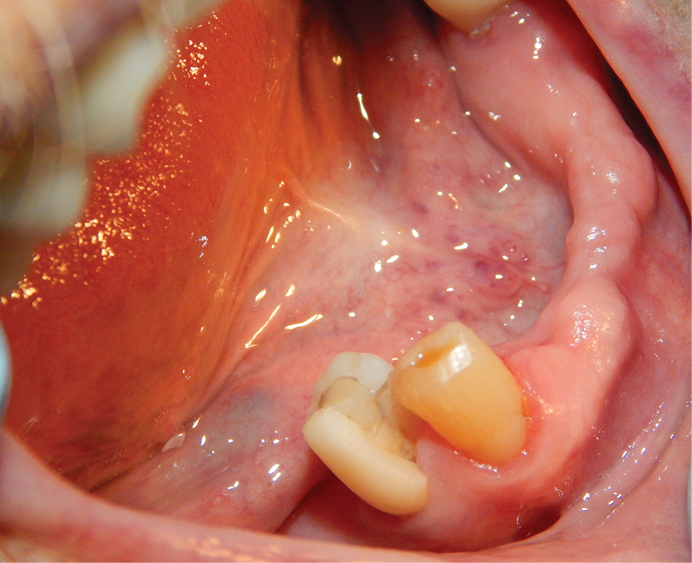

Figure 1: No. 28 crown that had fractured after root canal therapy was completed